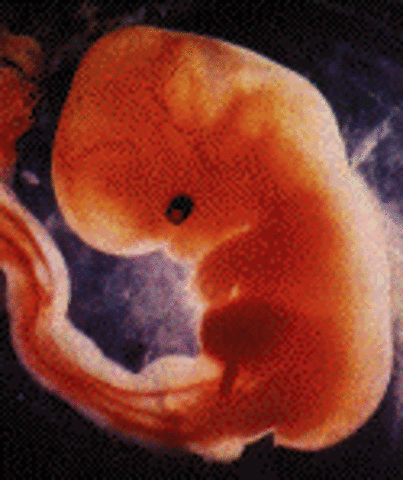

• Week 5 of First Trimester

Week 5 of First Trimester

Implantation continues with the Blastocyte still dviding, this begins the embyronic stage.

Facts:

1)The embryo grows from a tiny speck about 2mm - the size of a pin head.

2) During this stage the embryo will start to recieve oxygen and nutrition.